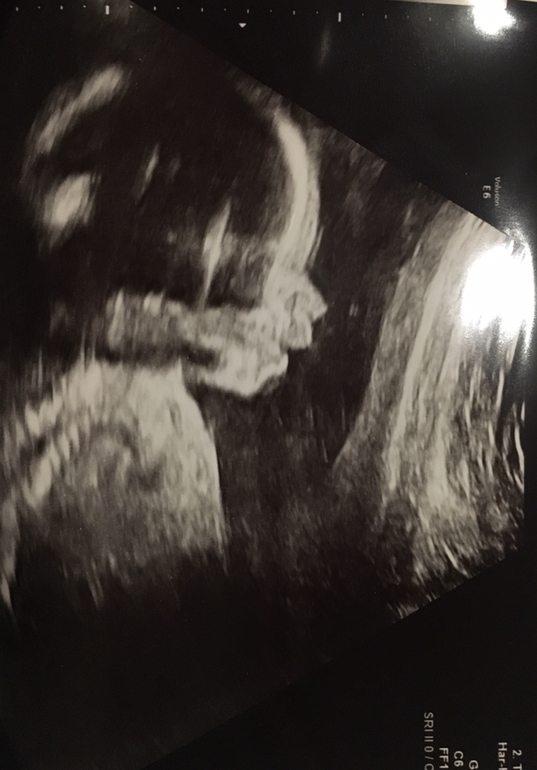

22 недели фото узи

УЗИ, КТГ, доплерПосмотрите вот, мне напоминает Якубовича с усами... Ляля Якубович млин)))

хотя я на 2 скрин пришла, врач смотрит, улыбается "какая ушастенькая и курносая".

А по-моему, милаха, и ничуть на Якубовича не похожа)

Заявляю как знаток: я в детстве его усов жутко боялась, а тут даже близко ничего такого нет))